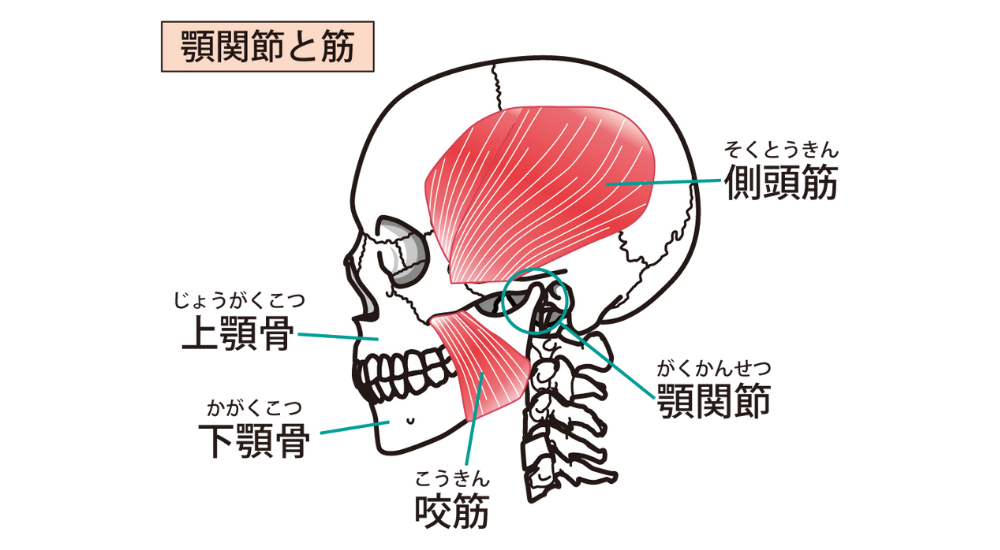

- 咬筋・側頭筋: 顎周りの筋肉。ストレスや不良姿勢による噛みしめで硬くなりやすいです。